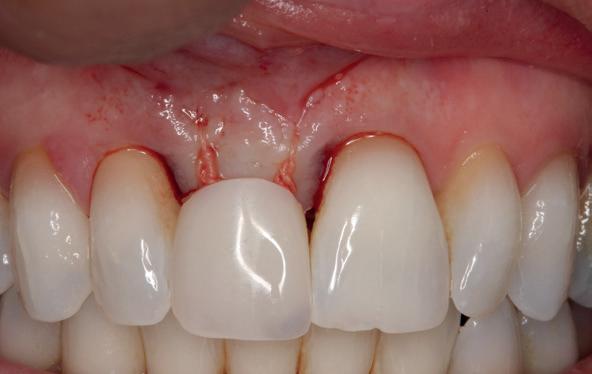

Implantologische behandelingen in het esthetische front vragen meer dan technische vaardigheid alleen. Ze vragen om overzicht, timing, vertrouwen en een team dat als vanzelf samenwerkt onder druk. Juist bij complexe casussen, waarin angst, infectie en hoge esthetische verwachtingen samenkomen, wordt zichtbaar hoe bepalend de rol van de tandartsassistent is.

Deze casus beschrijft een uitgebreide immediate implantaatbehandeling bij een patiënt die door meerdere collega’s werd geweigerd. Niet omdat de mogelijkheden ontbraken, maar omdat de complexiteit vroeg om een perfect afgestemde samenwerking. Het verhaal laat zien hoe de assistent in zo’n traject veel meer is dan een uitvoerende kracht of “mal”, maar een dynamische surgical guide die het proces mede stuurt, bewaakt en mogelijk maakt.De patiënt: wanneer alles samenkomt

Na het klinische onderzoek volgde het röntgenologisch traject. De CBCT liet precies zien wat we al vreesden: een front waarin het bot onregelmatig was, duidelijke radiolucenties rond de pijlers en een infectiegebied dat zich onder vrijwel de gehele brug had verspreid. Tegelijkertijd was er ook potentie. Net voldoende botstructuur om immediate implantaatplaatsing te overwegen, mits alles perfect gepland zou worden.